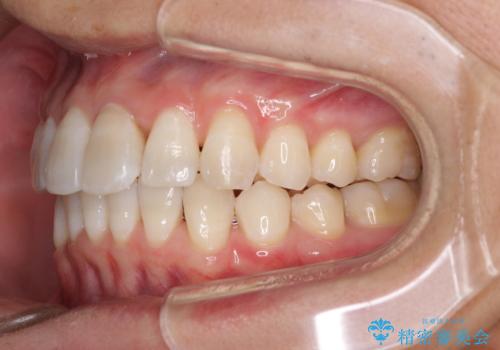

前歯のデコボコを治したい インビザラインによる矯正治療

- 前歯のデコボコを治したいとのことで来院された患者様です。

上下顎ともに歯列全体の後方移動とIPR(歯と歯の間を削る)によってデコボコが解消するように設計し、インビザラインにより治療を行うこととしました。

矯正治療後、前歯の形と色が気になるとのことでしたが、大分前に失活している(神経が取り除かれている)歯であり、その影響で変色しているため、オールセラミッククラウンによる補綴治療をおすすめいたしました。